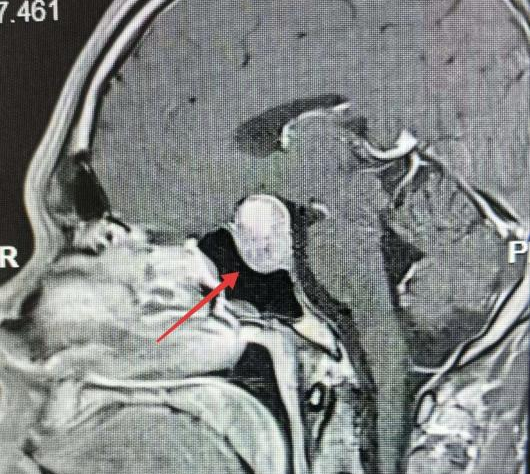

头颅MRI影像一出来,所有的疑惑瞬间解开——李先生大脑深处、颅底正中的鞍区,竟长出了一枚巨大的生长激素垂体腺瘤。

确诊后,李先生被紧急转入神经外科救治。影像显示,李先生的肿瘤向上紧紧压迫视神经与下丘脑,后方毗邻脑干这一生命中枢,周边更是环绕着颅内多条重要大血管——这相当于在大脑最凶险的核心区域,埋藏了一颗随时可能引爆的“定时炸弹”,稍有不慎便会引发致命危险。

“患者已突发垂体瘤急性卒中,瘤体内出现出血坏死,随时可能引发失明、剧烈头痛、昏迷休克,短短几小时就可能危及生命,必须立即手术干预。”南通市第一人民医院神经外科副主任医师王学建查看完李先生的报告后立即组织会诊,第一时间为他制定了个性化的手术方案——经鼻蝶微创内镜手术。